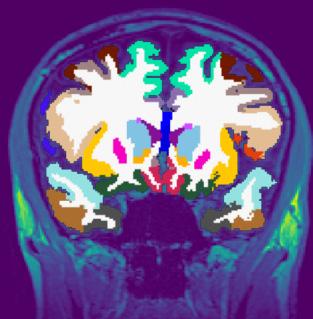

Around four years ago we were approached by Oxford Brain Diagnostics (OBD), a company that has developed a new technique to analyse normal MRI brain scans, called Cortical Disarray Measurement (CDM). It’s a technique that can identify microscopic changes in the brain which are thought to be linked to Alzheimer’s disease pathology.

CDM uses the same brain scans that are already used as part of dementia

diagnosis, but a specialised sequence on the scanner which looks at the flow of water through the brain. This can provide information on tissue microstructure in the grey matter of the brain, and changes that are linked to potential underlying pathology.

Currently, an MRI scan is used clinically to look at basic structure of the brain to identify brain shrinkage. But gross volume loss in the brain is not seen until the later stages of the disease, so it often provides little information in the early Alzheimer’s and mild cognitive impairment stages. A more sensitive measure could help improve earlier detection and diagnosis.

Although OBD had promising preliminary data on the imaging technique, they needed to complete a larger scale analysis to see whether it could be effective in a real-world population. We developed the CONGA trial to see whether we can use this CDM technique to identify

changes associated with Alzheimer’s earlier than what’s currently available.